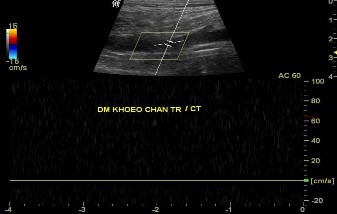

Siêu âm Doppler mạch máu (đặc biệt là siêu âm Doppler màu) là một xét nghiệm để chẩn đoán chấn thương mạch máu thông dụng có thể đưa ra những hình ảnh tổn thương có giá trị như vị trí huyết khối lòng mạch, mất phổ động mạch dạng sóng 3 pha (ảnh 1.4) với độ nhạy và độ đặc hiệu lần lượt là 95% và 99%, được tiến hành nhanh chóng nên không kéo dài thêm nhiều thời gian thiếu máu ngoại vi [49], [91].

Ảnh 1.4: Hình ảnh siêu âm Doppler: mất phổ sóng 3 pha động mạch khoeo

*Nguồn: theo Trịnh Vũ Nghĩa (2010)[19]